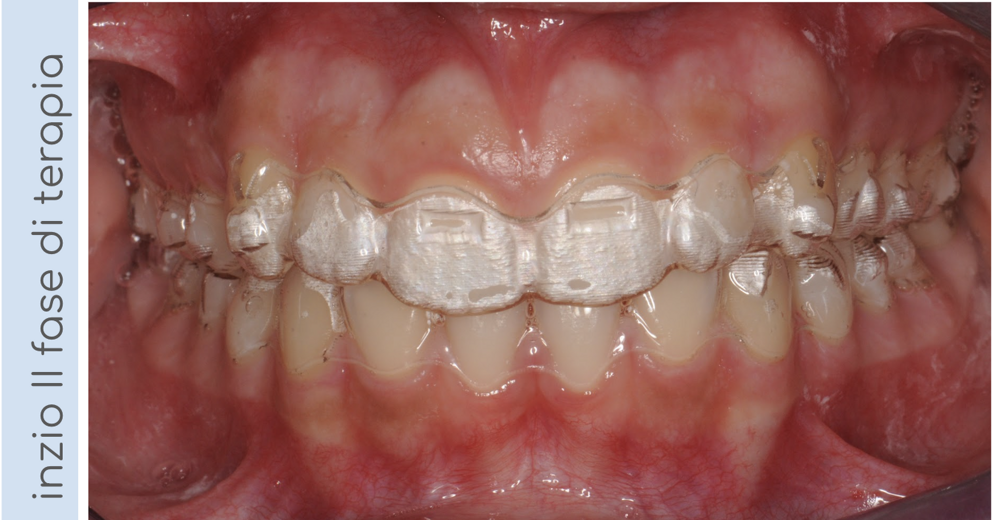

In questo caso, il paziente presentava un morso crociato posteriore a sinistra, intercettato precocemente e corretto in dentatura mista. Al termine della terapia intercettiva, una volta erotti tutti i denti permanenti, il nostro piccolo paziente ha iniziato una seconda fase di terapia con allineatori trasparenti per finalizzare il trattamento e allineare correttamente le arcate!